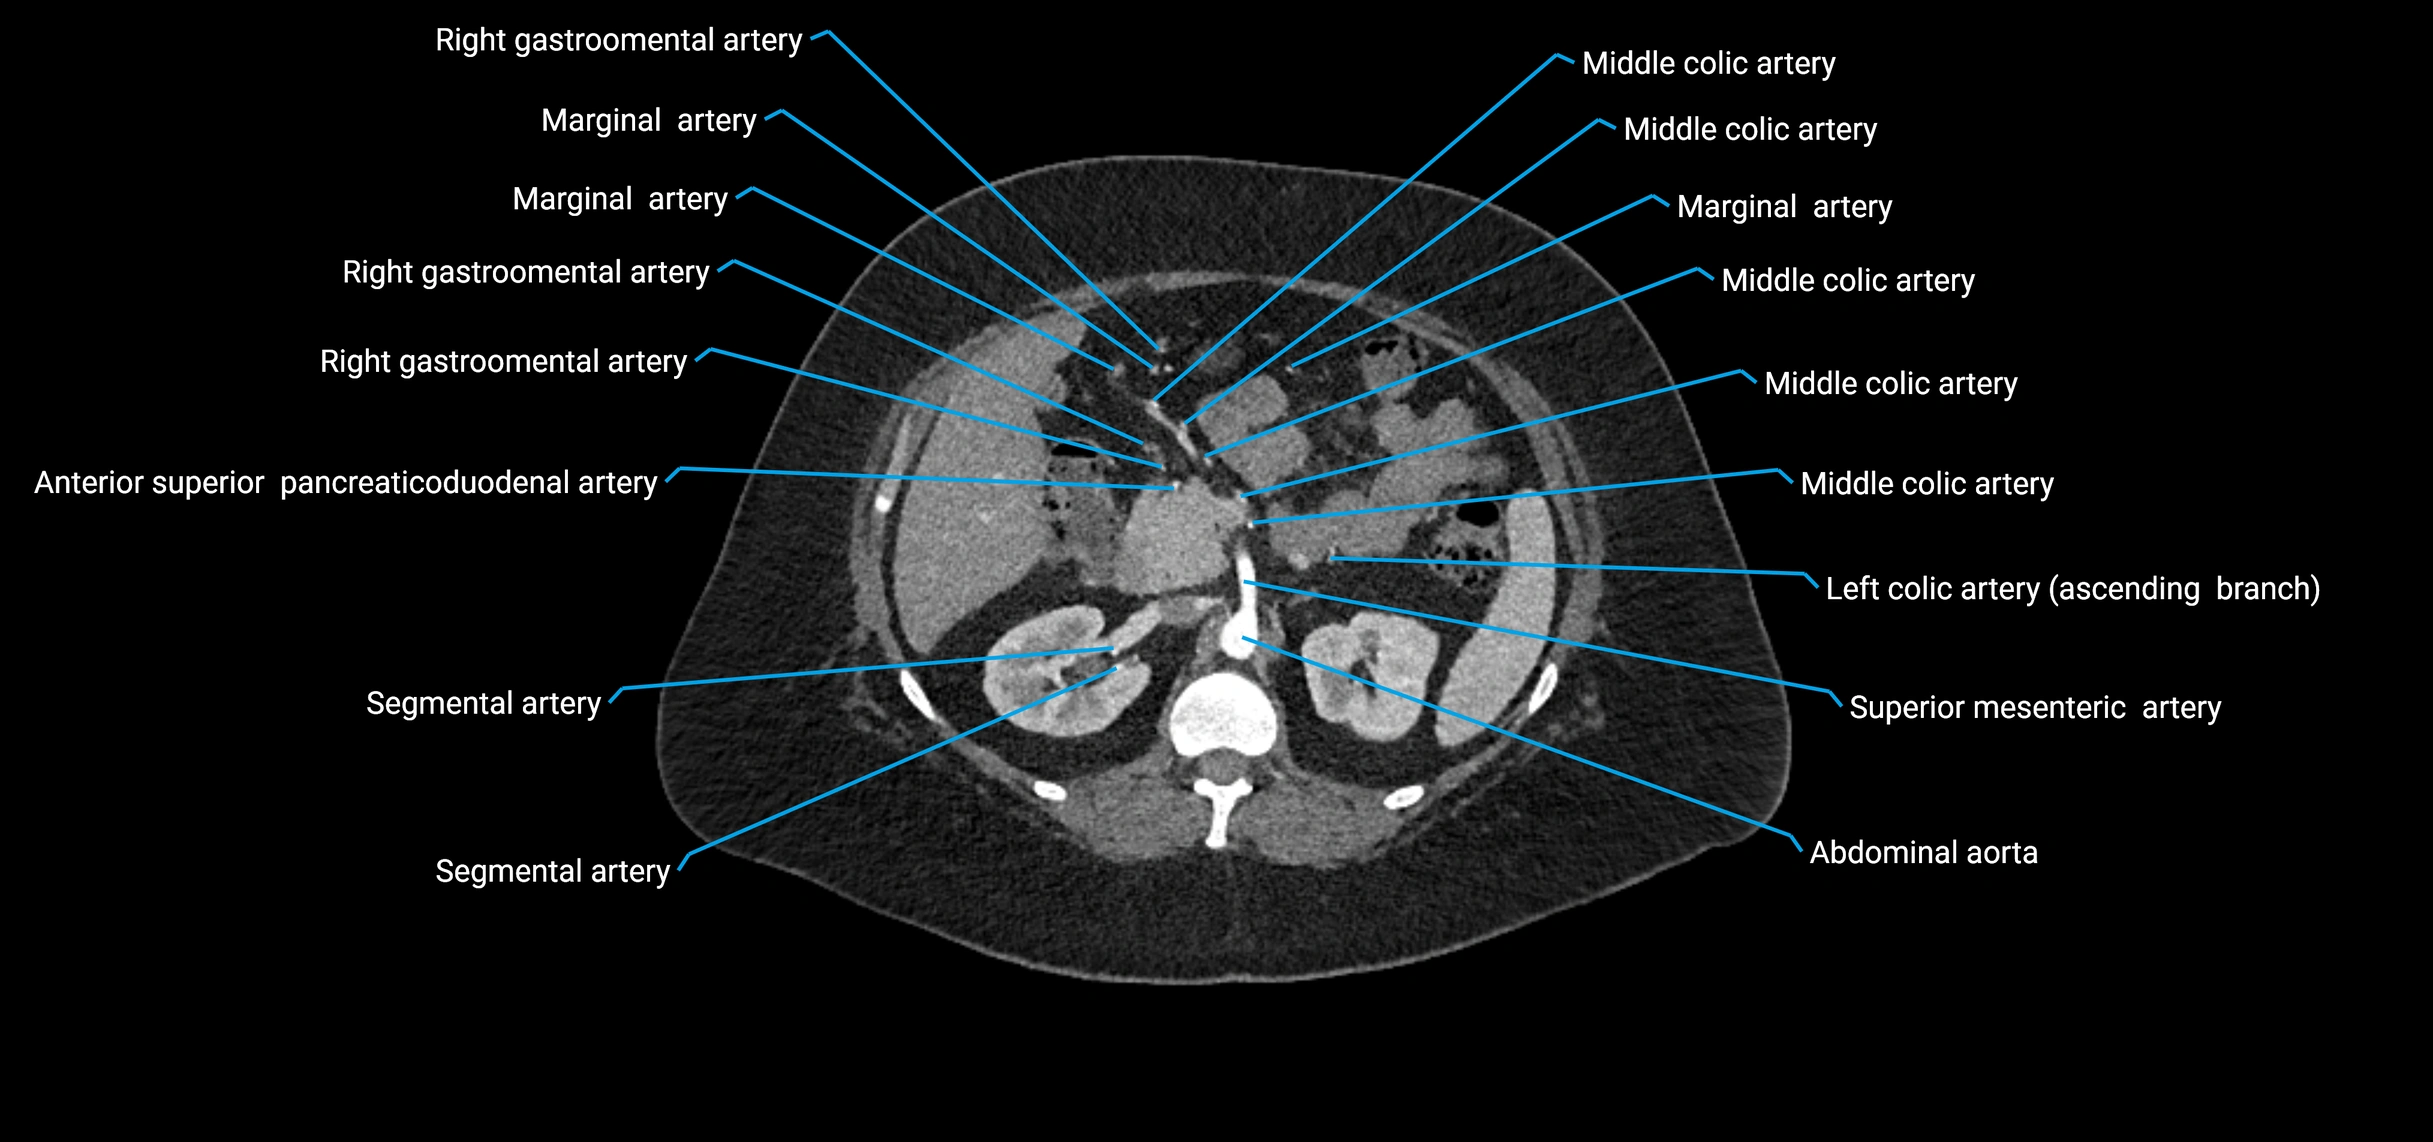

Contrast-enhanced CT (CTA):

• Gold standard for abdominal aortic imaging

• Provides excellent detail of lumen, wall, aneurysm, thrombus, and branch vessels

• Multiplanar and 3D reconstructions help in aneurysm measurement, stent graft planning, and dissection evaluation

• Detects acute rupture, traumatic injury, or occlusion with high sensitivity